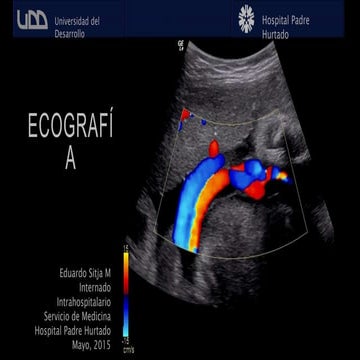

¿CÓMO HACEMOS

ECOGRAFÍA?

Sonda lineal

EFECTO PIEZOELECTRICO

MODO B (BRIGHT)